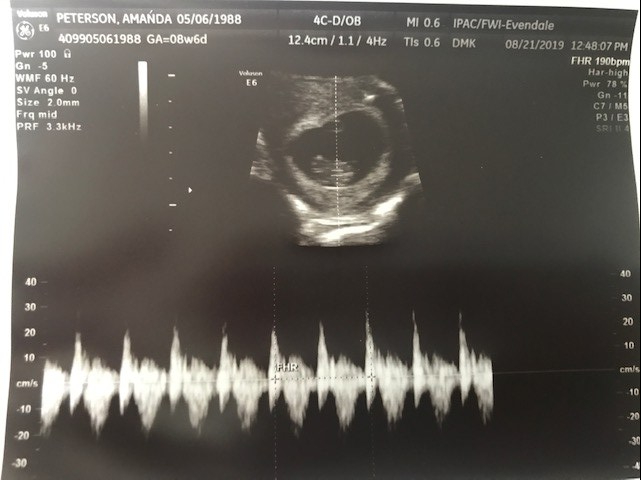

We arrived at the appointment, and the ultrasound tech calls us back. She’s new. Not the same tech I have seen with previous pregnancies, which was a relief. Not that the previous tech wasn’t a nice gal, but I just have horrible memories associated with her voice. The new tech wants to do the ultrasound on my belly instead of transvaginally. I shot Justin a terrified look like, “here we go again” because previously we have never been able to see anything with a belly ultrasound. I couldn’t look – I stared at the ceiling with tears in my eyes, assuming she’s not going to see much. Then I heard her say, “There it is! Oh, and squirming around!” I looked and she was right. There was a baby, with a fast flickering little heartbeat. We both let out huge sighs of relief and started bawling!

After a minute or two, the ultrasound tech asked me to calm down so my belly would quit moving. Then, suddenly, we heard the sweetest sound our ears have ever heard – a heartbeat. “Measuring at about 190 beats per minute. That’s probably as high as yours is right now!,” she joked. Baby measured 8 weeks and 5 days, just one day off from my dates, which is perfectly normal. Again, we let out huge sighs of relief and sobs. We explained that we have never had a positive outcome during an ultrasound before, and I dubbed her my new best friend.

After the ultrasound they sent us back into the waiting room until my doctor was ready to see us. I snapped this quick photo while we waited, and sent it to my mom with the words, “WE HAVE A HEALTHY BABY!!!!!!” until I had time to fill her in.